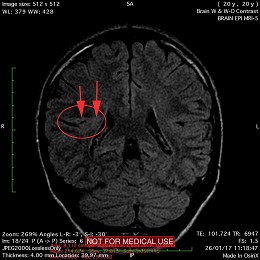

This recent MRI exam WITHOUT Contrast in IHC, revealed a subtle congenital malformation of cortical development within right parietal lobe.

A subtle linear band intensity extending between deep posterosuperior aspect of right Sylvian fissure and posterior aspect of corpus of right lateral ventricle (isointense with gray matter on all sequences). These MRI findings strongly suggest "Type II (Taylor type) focal cortical dysplasia (transmantle cortical dysplasia)" or "transmantle gray matter heterotopia". Virtually, they may be representing two different names for the same entity.

Secondary hippocampal sclerosis is identified, bilaterally (secondary to long-term intractable epilepsy).